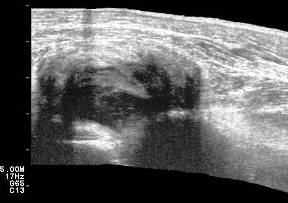

En Ultrasonido articular y de partes blandas se observa importante acumulo de líquido sinovial en bolsa sub cuadricipital, hipertrofia marcada de la sinovial, cambios degenerativos con afinamiento del cartílago articular, hacia la parte posterior de la pantorrilla en región de los gastronemios, masa compleja de 15 cm de largo por 6 cm de ancho con zonas de induración de aspecto tumoral que alternan con zonas quísticas de contenido líquido, tabicados, de aspecto crónico , se toman muestras de líquido y tejido de las zonas solidas por (Biopsia por Aspiración con Aguja Fina) BAAF guiada por US.

Ultrasonido de la rodilla donde se observa gran acumulo de líquido sinovial en bolsa sub cuadricipital, aumento de la celularidad del líquido, con imágenes de tabiques. Imagen 8

Imagen 8. Ultrasonido de la rodilla con acumulo de líquido sinovial